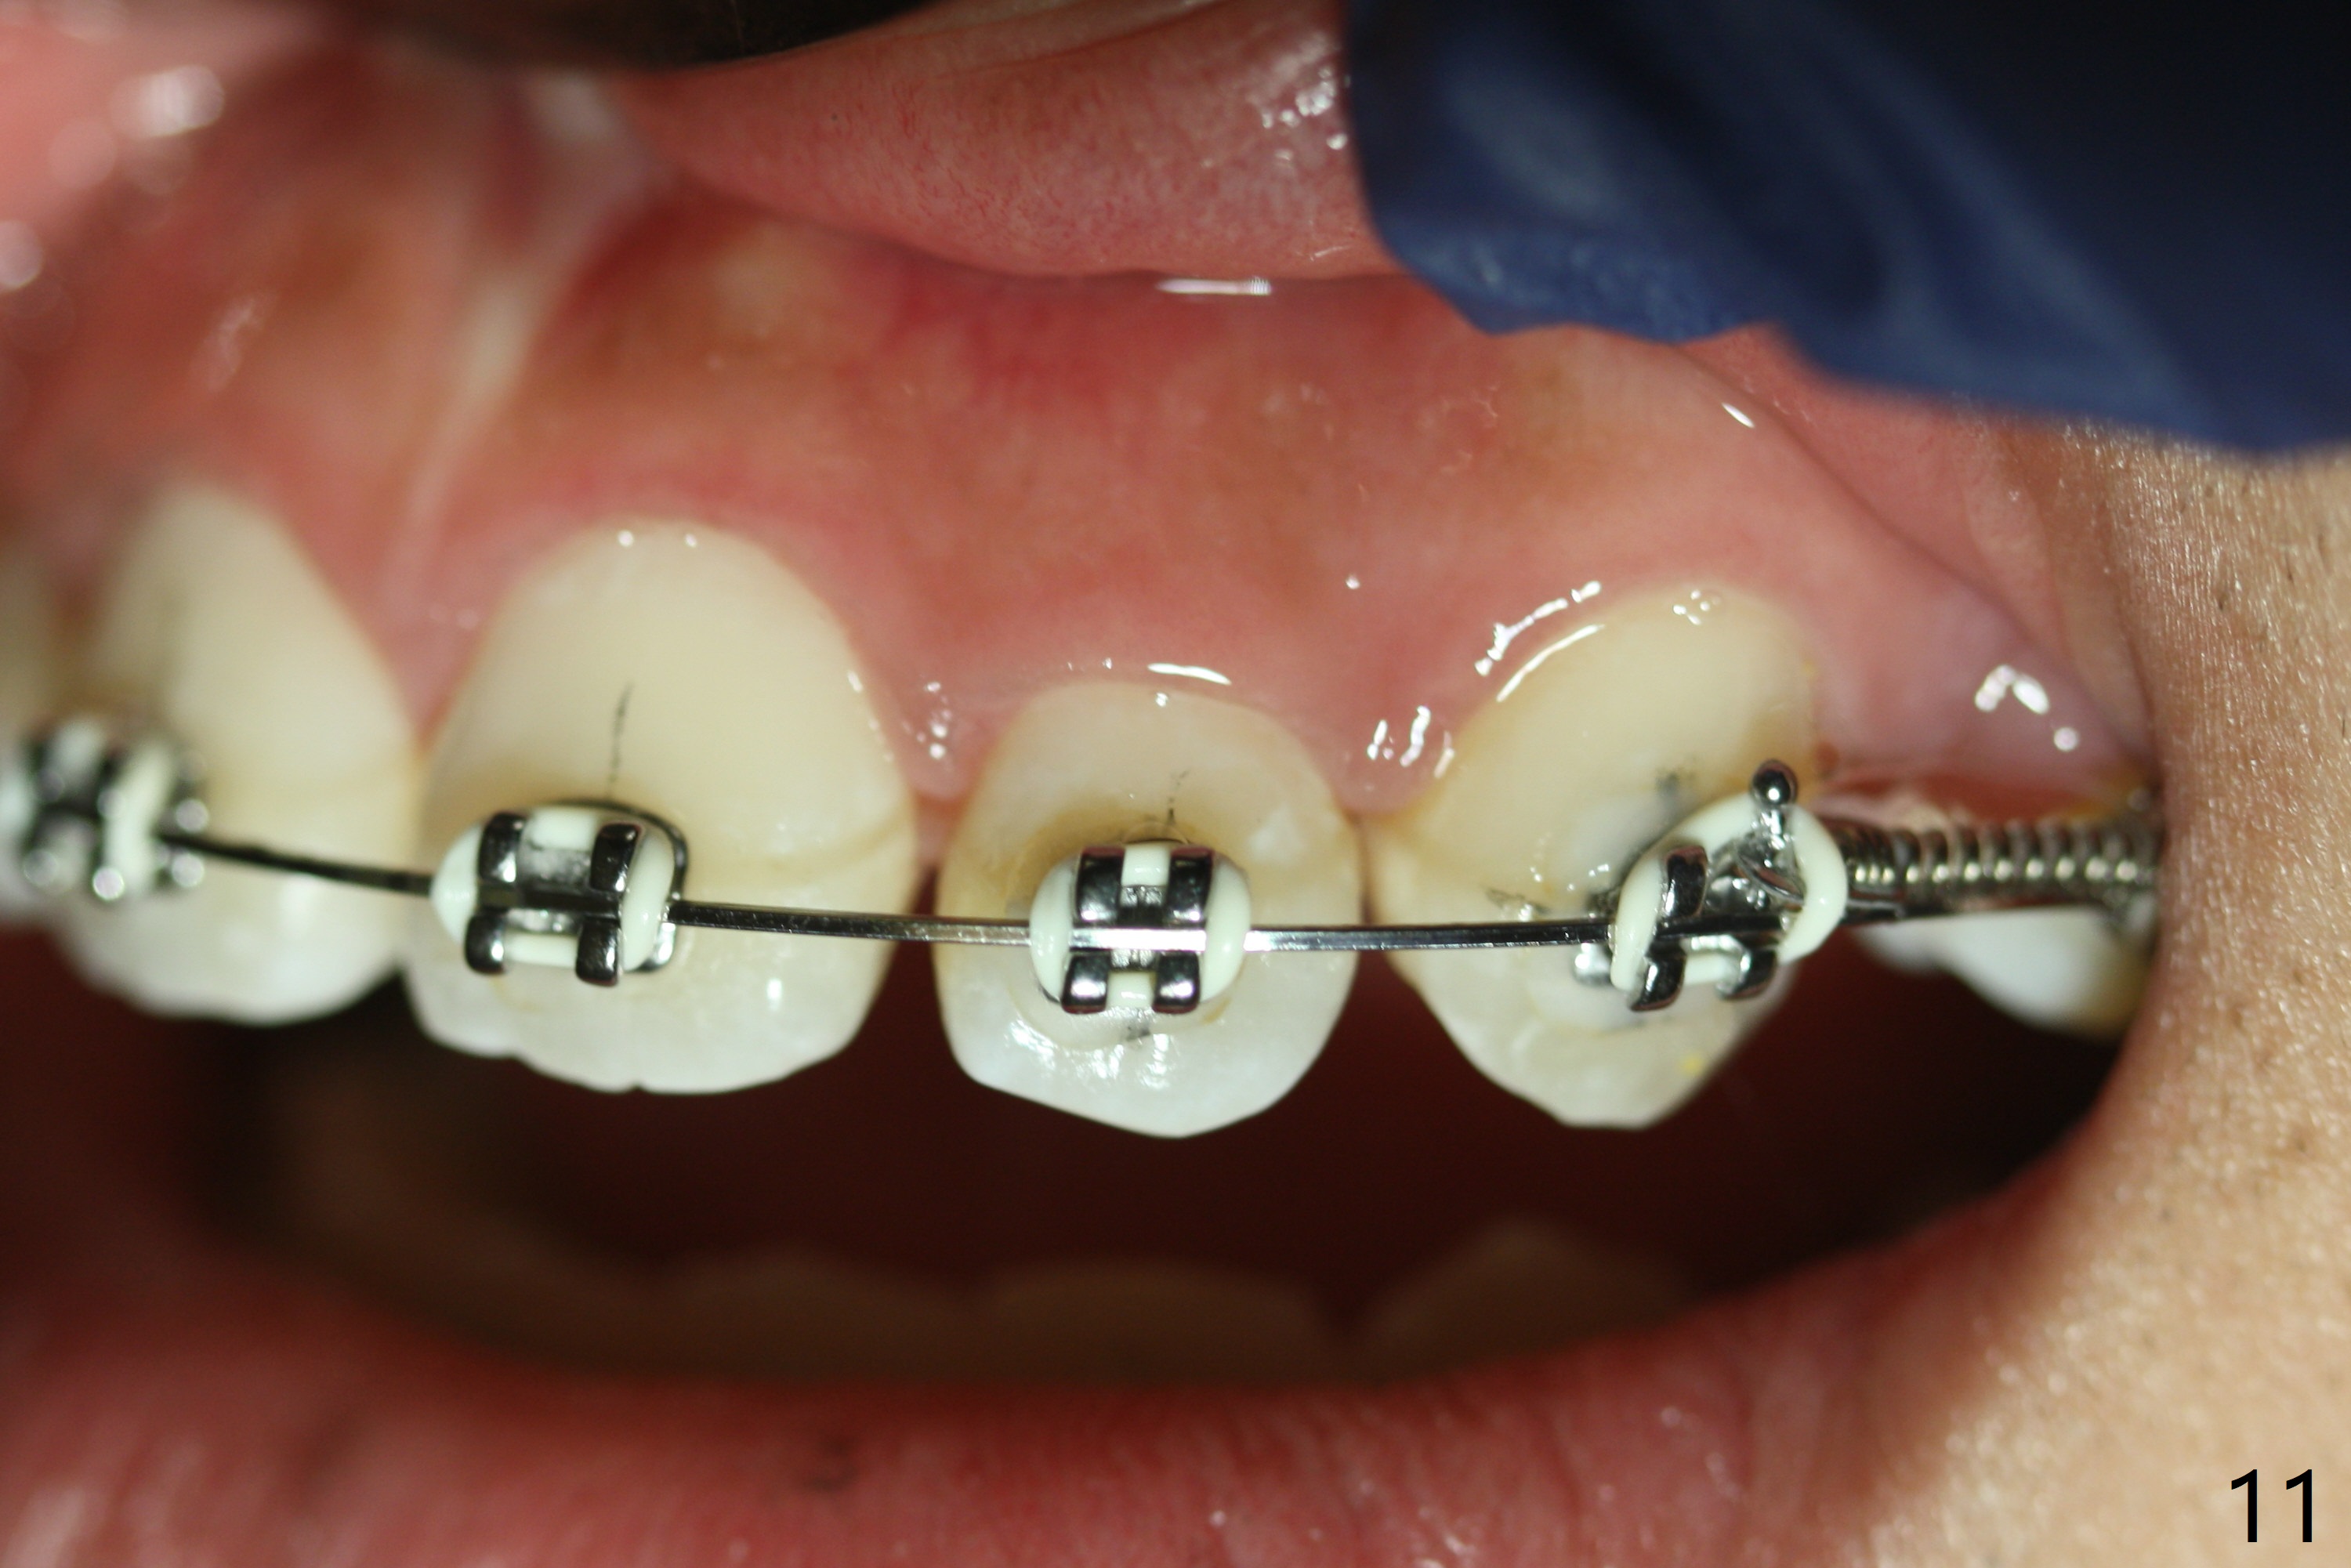

Anterior open bite is corrected with composite in L7s with elastic box bilaterally. UR3 is fully distalized after a closed spring is placed between UR3-7. Sling shot is applied for UR2 cross bite correction with UR3-6 ligature wire and U3-7 closed spring (latter 2 to keep position of UR3). Three weeks of closed spring between UL3 and 6, UL2 is also distalized because of periodontal ligament between the neighboring teeth (Fig.11 (10.5 months post banding; 16x22 wire placed for further retraction (overjet))).